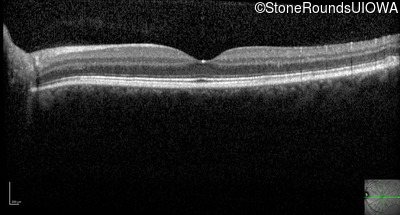

Optical Coherence Tomography - Right - 20/15 -1 sc

Exemplar / OCT Stack